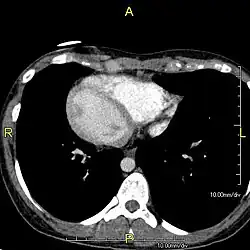

- Situs inversus: condição congênita onde os órgãos do tórax e abdômen estão transpostos;

O portador da discinesia ciliar primária pode apresentar tosse produtiva crônica e infecções respiratórias recorrentes. Como o diagnóstico tende a ser tardio e de exclusão, pode haver comprometimento progressivo da função pulmonar e baqueteamento digital (alteração caracterizada pelo aumento do diâmetro das falanges distais e alterações das unhas) em pacientes mais velhos. Situs inversus.